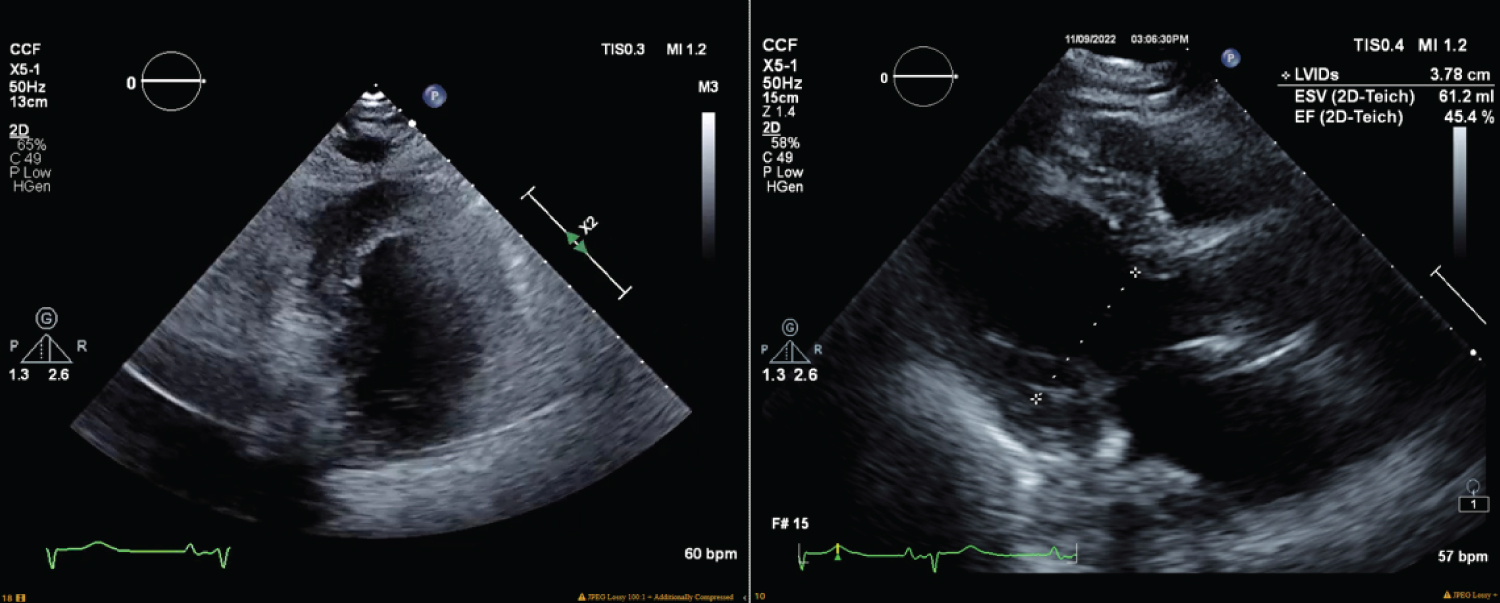

Transesophageal echocardiography was performed intraoperatively (Figure 1), six hours postop (Figure 2), and five days postop (Figure 3). EKG performed intraoperatively following ROSC demonstrated sinus rhythm with a borderline repolarization abnormality and a prolonged QT interval of 444 ms and QTc of 451 ms. Notably, there was no ST segment elevation present.

Figure 2: Transesophageal echocardiogram performed six hours after the cardiac arrest, revealed left ventricle ejection fraction of 45%, moderate right ventricular dilation, moderate right atrial dilation, and a mildly hypokinetic left ventricular wall, septum, apex, and inferior wall. View Figure 2